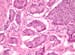

Multiple tubers in a child with tuberous sclerosis, normal intelligence, and well-controlled seizures. High tuber count does not invariably mean poor neurological outcome.

All tubers are not equal. This child has a smaller number of tubers than the patient shown in the previous image, but the tubers are larger in size. She too has normal intelligence and is seizure free on medication.